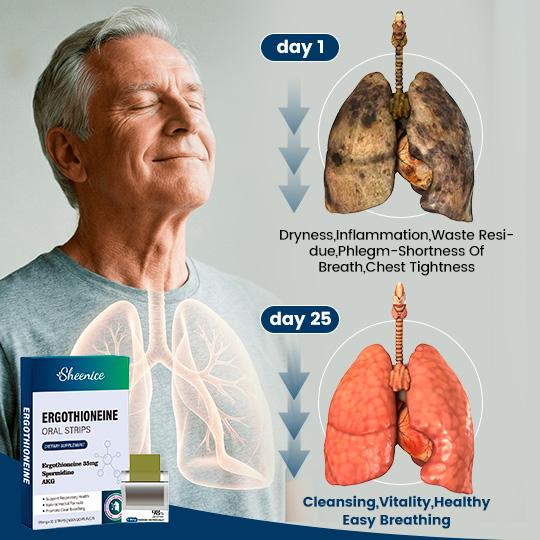

Sheenice is an organic, plant-based dissolvable strip that supports COPD relief and easier breathing, helping reduce airway mucus, lung buildup, asthma discomfort, and inflammation.

Relieves cough and shortness of breath

Helps clear mucus and impurities from the lungs

Improve lung Capacity

Helps with asthma and COPD

90% of COPD patients reported their lung function returned to normal and their breathing became smoother after treatment.